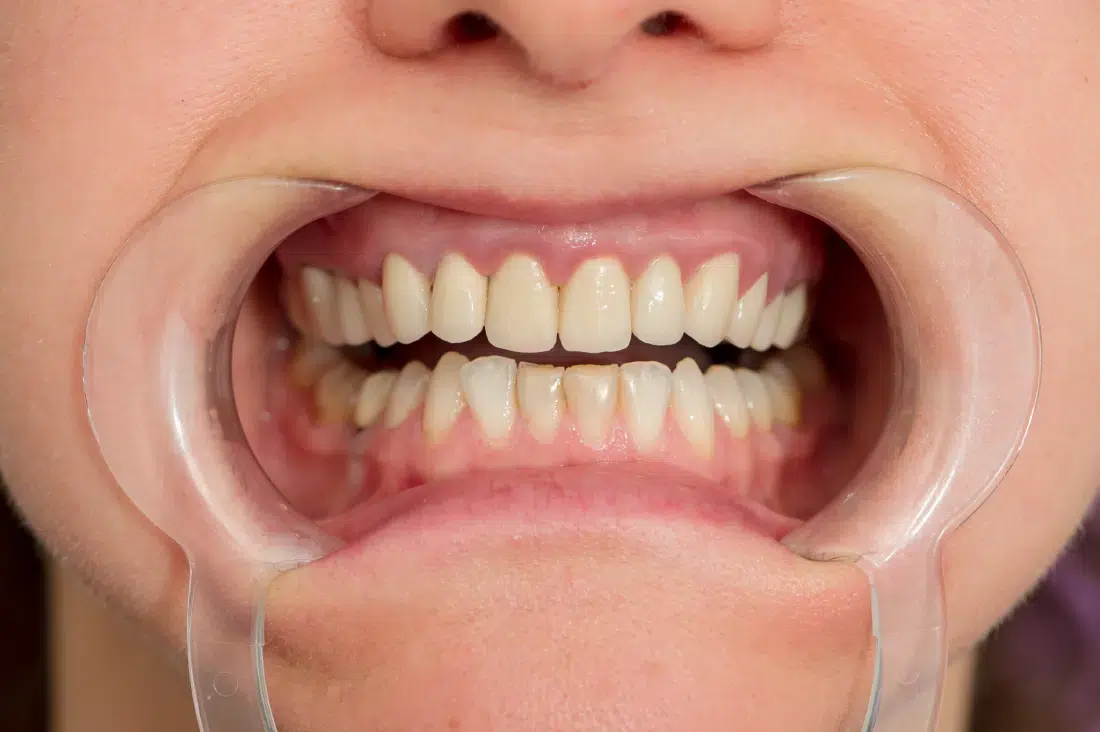

Înainte

Provocarea acestui caz a fost tratarea minim invazivă a dinților restanți, în urma înlocuirii coroanelor vechi și obținerea unor dinți cu un volum mai mare pentru echilibrarea zâmbetului într-un aspect cat se poate de natural.

Pacientă a beneficiat de corecție gingivală cu laser pentru uniformizarea asimetriilor gingivale, tratamente endodontice de canal sub microscop, obturațiile vechi (plombe) schimbate cu materiale de compozit cu particule nanoceramice, și fațete dentare din ceramică presată E-Max.

Termen de finalizare 2 săptămâni de la amprentarea finală.